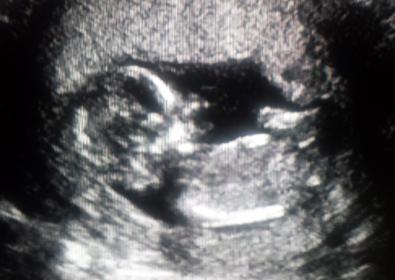

This is from today, 12 weeks 4 days! I'm not the most patient person and the wait to reach nub theory time territory has been brutal lol. Based on nub theory, what am I having?!

Maybe girl but not the best pic, anymore at all?

Very slight boy lean, but not a good pic, sorry!